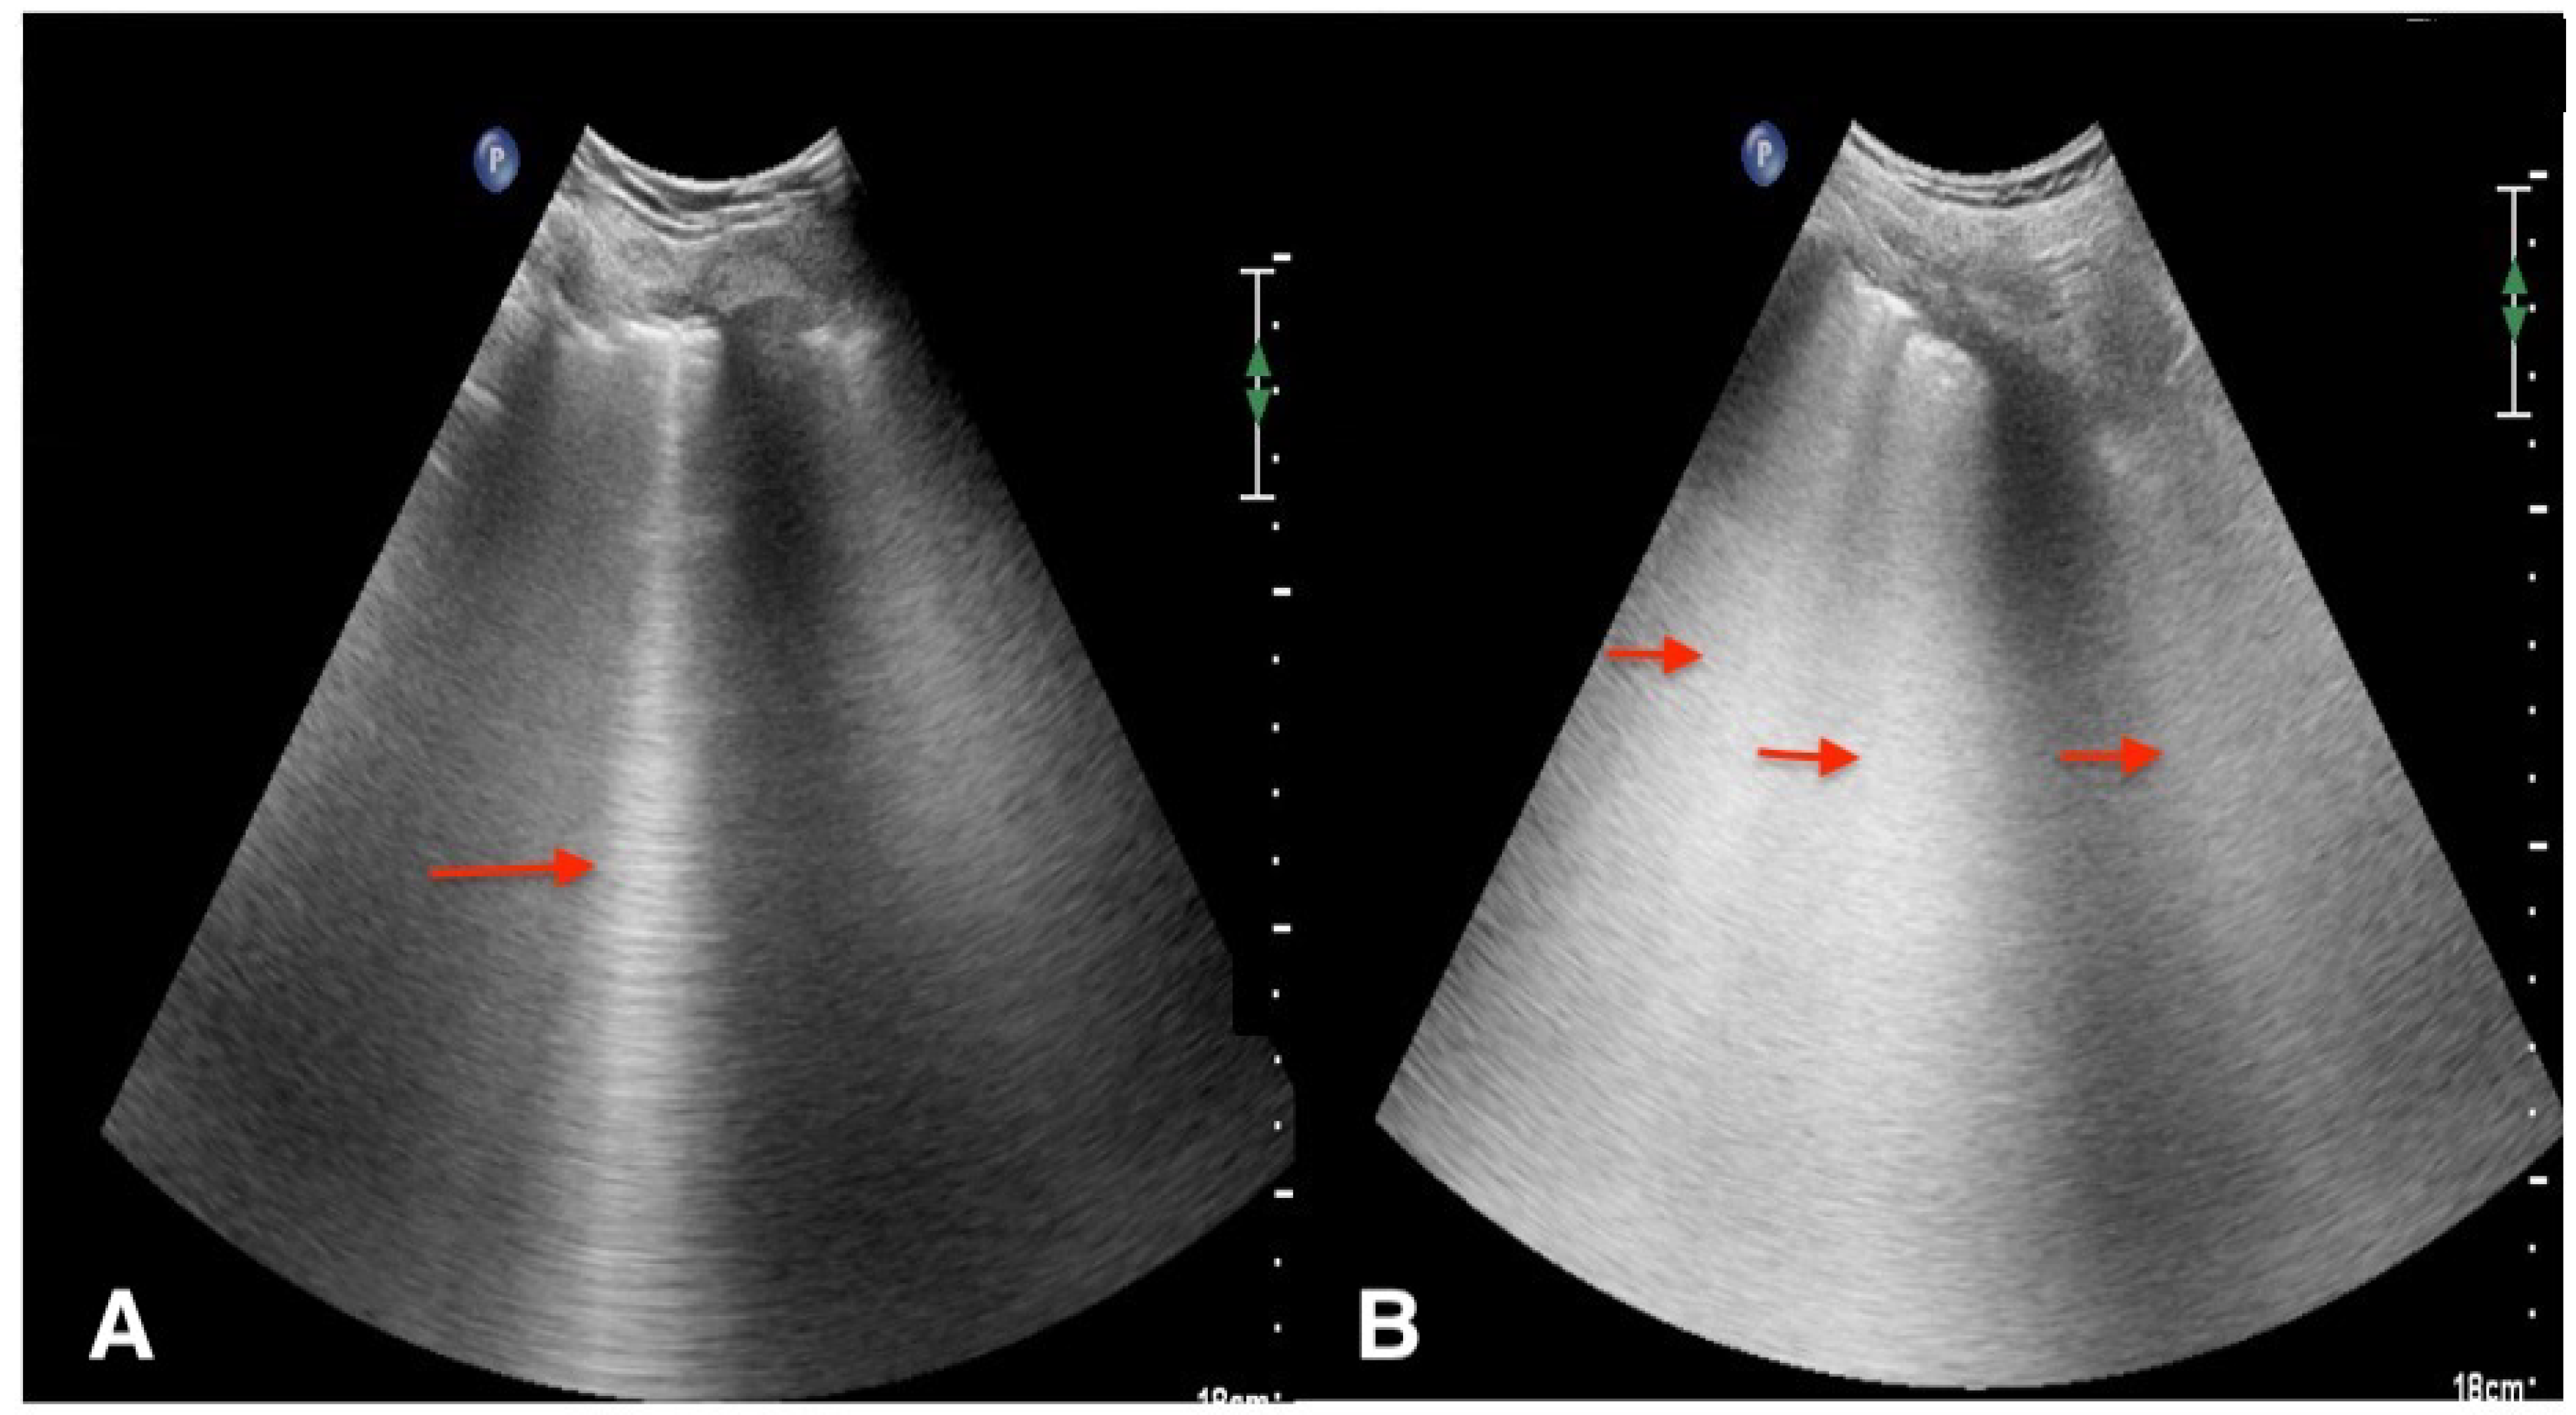

Artifacts

Real Images

Pneumothorax